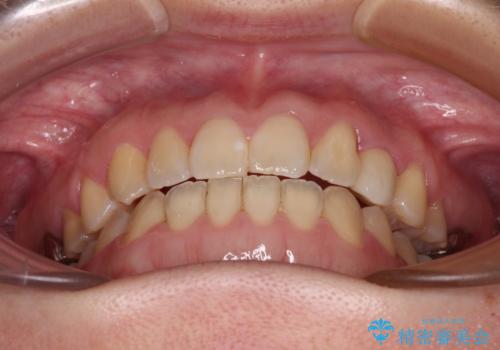

受け口で開咬を急速拡大装置とインビザラインで改善 欠損部分はインプラントにて補綴治療

矯正治療が終わるタイミングに合わせてインプラントの埋入を行っていたので、矯正治療を終了すると同時にセラミック補綴治療を行えました。

インビザラインの装着時間が不十分であったので、治療期間は長期間となりました。